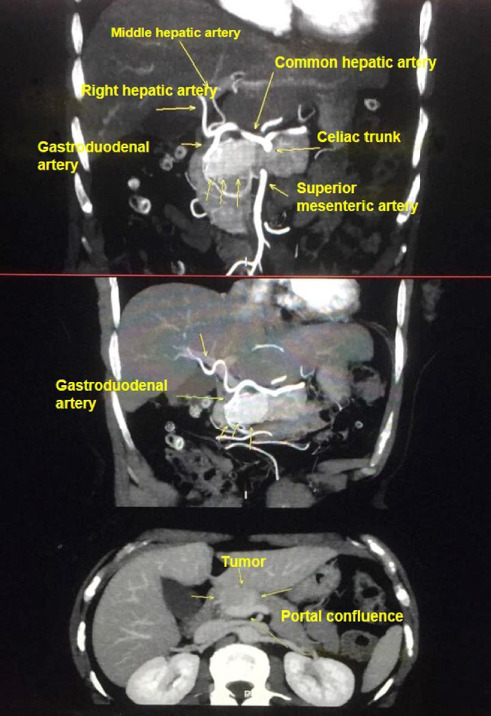

胰腺固体型浆液性囊腺瘤(SSCA)是胰腺囊性肿瘤中极为罕见的良性疾病。虽然其影像学特征不具有典型的病理特征,但可能与其他实体胰腺肿瘤相似。特别是,它在放射学研究上与胰腺神经内分泌肿瘤(pNEN)非常相似。我们报告的情况下,一个67岁的妇女谁提出腹痛。术前腹部磁共振造影(MRI)示胰腺实性高血管病变,尺寸为3.5 × 2.2 × 1.9 cm,动态成像明显增强。最初怀疑为无功能胰腺神经内分泌肿瘤。患者行腹腔镜胰十二指肠切除术。组织病理检查显示为浆液性囊腺瘤,一种罕见的胰腺囊肿亚型。患者无症状,术后7年无复发或残留疾病的迹象。本病例强调了仅凭影像学区分实体型浆液性囊腺瘤与其他胰腺病变的诊断挑战,强调了病理在明确诊断中的作用。

Solid-type serous cystadenoma (SSCA) of the pancreas is an extremely rare benign condition among pancreatic cystic neoplasms. Although the imaging characteristics are not pathognomonic, this entity may mimic other solid pancreatic tumors. In particular, it can closely resemble a pancreatic neuroendocrine neoplasm (pNEN) on radiologic studies. We report the case of a 67-year-old woman who presented with abdominal pain. Preoperative abdominal magnetic resonance imaging (MRI) with contrast demonstrated a solid, hypervascular lesion at the pancreas, measuring 3.5 × 2.2 × 1.9 cm, with marked enhancement on dynamic imaging. A nonfunctioning pancreatic neuroendocrine tumor was initially suspected. The patient underwent laparoscopic pancreaticoduodenectomy. Histopathologic examination revealed a solid variant of serous cystadenoma, a rare subtype of pancreatic cysts. The patient remains asymptomatic, with no evidence of recurrence or residual disease at 7 years postoperatively. This case highlights the diagnostic challenge of distinguishing solid-type serous cystadenomas from other pancreatic lesions based on imaging alone, underscoring the role of pathology in definitive diagnosis.